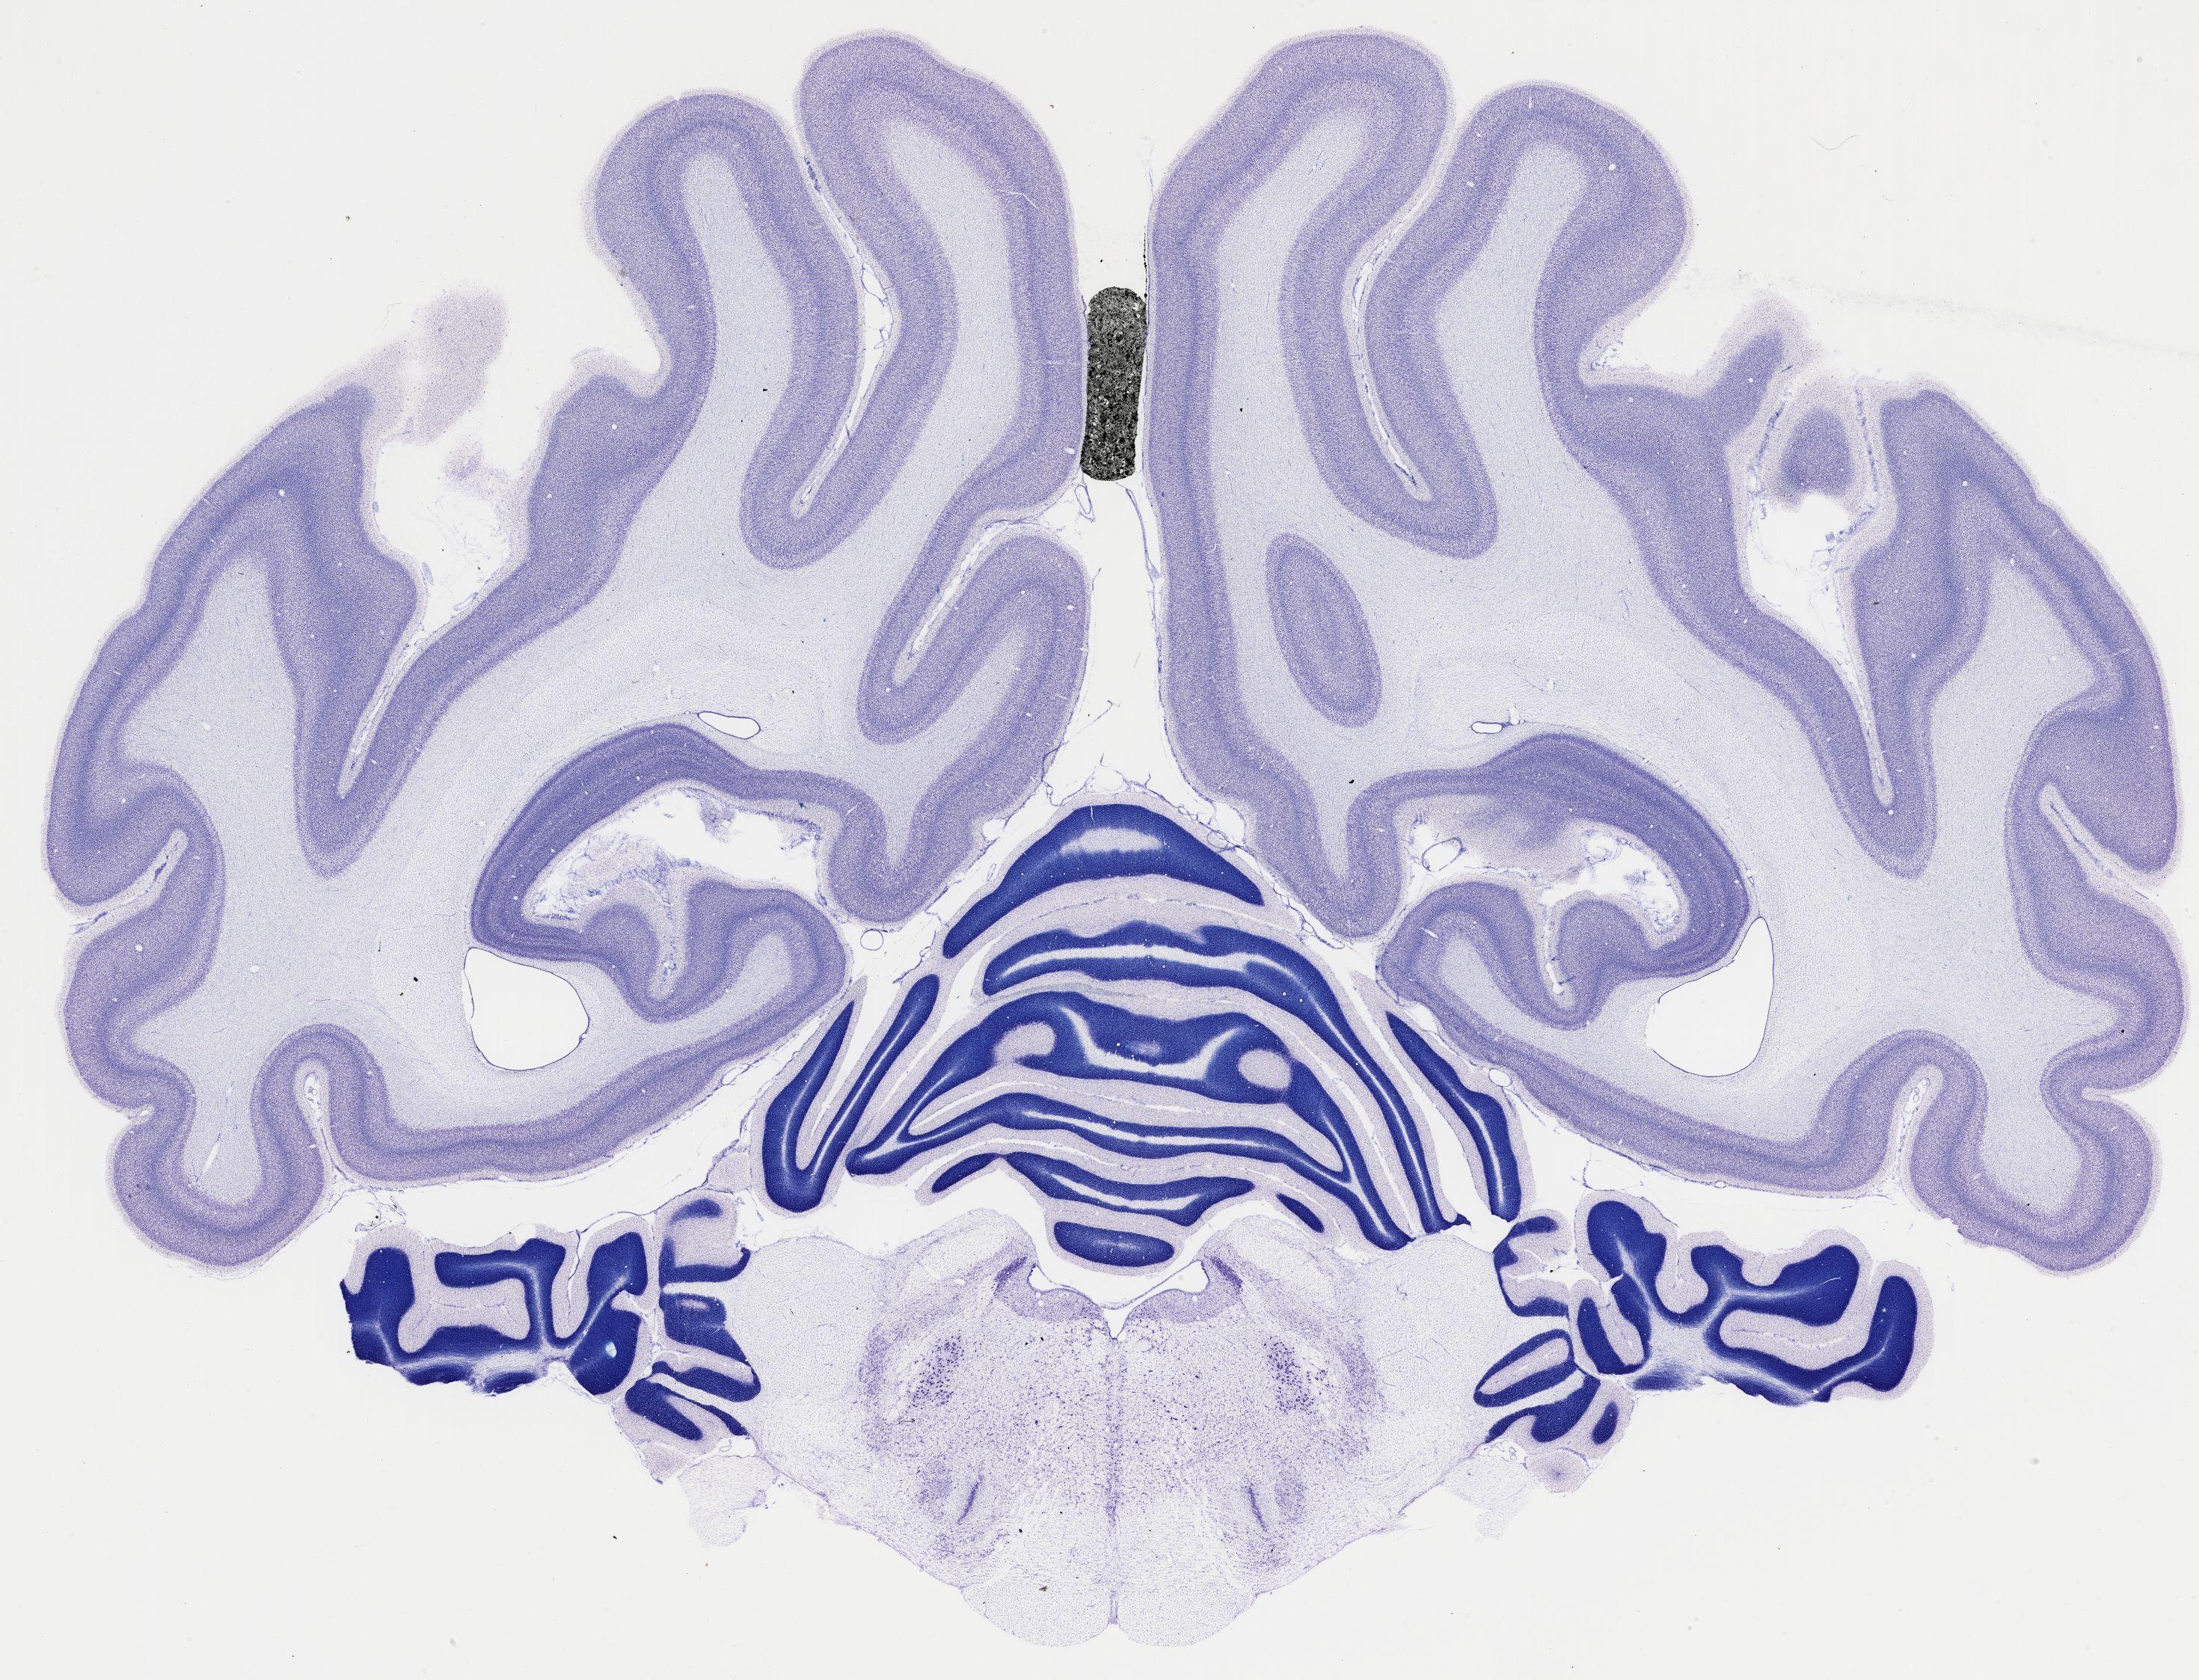

Datasets -> Chlorocebus Aethiops -> Nissl, coronal, histo, Whole-Brain, adult

[ Metadata ]   ·   Source: NeuroScience Associates

Displaying Sections 481 thru 520 of 740 Sections for this Dataset

thumbnail

521